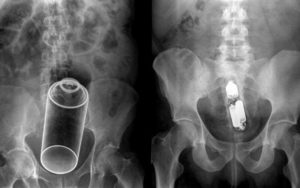

Врач может отыскать инородное тело в заднем проходе во время пальцевого исследования прямой кишки. Также инородные тела определяются путем рентгенологического исследования.

Для того, чтобы выяснить, повреждена или нет стенка толстой кишки, проводится инструментальное обследование — ректороманоскопия и рентгенография (ирригоскопия).

Затем может потребоваться обследование с помощью ректоскопа, а также рентген брюшной полости для определения точного расположения инородного предмета.

У всех больных инородные тела (бутылки, табакерка, рог) располагались горлышком вверх и отстояли от внутреннего сфинктера на расстоянии от 4 до 11 см.

Верхняя часть тела и горлышко бутылки проникали в сигмовидную кишку и отчетливо прощупывались через переднюю брюшную стенку слева от средней линии. Иногда было видно выстояние брюшной стенки, вызываемое инородным телом.

При пальпации со стороны передней брюшной стенки инородное тело представлялось подвижным в свободной части и фиксированным в глубине малого таза.